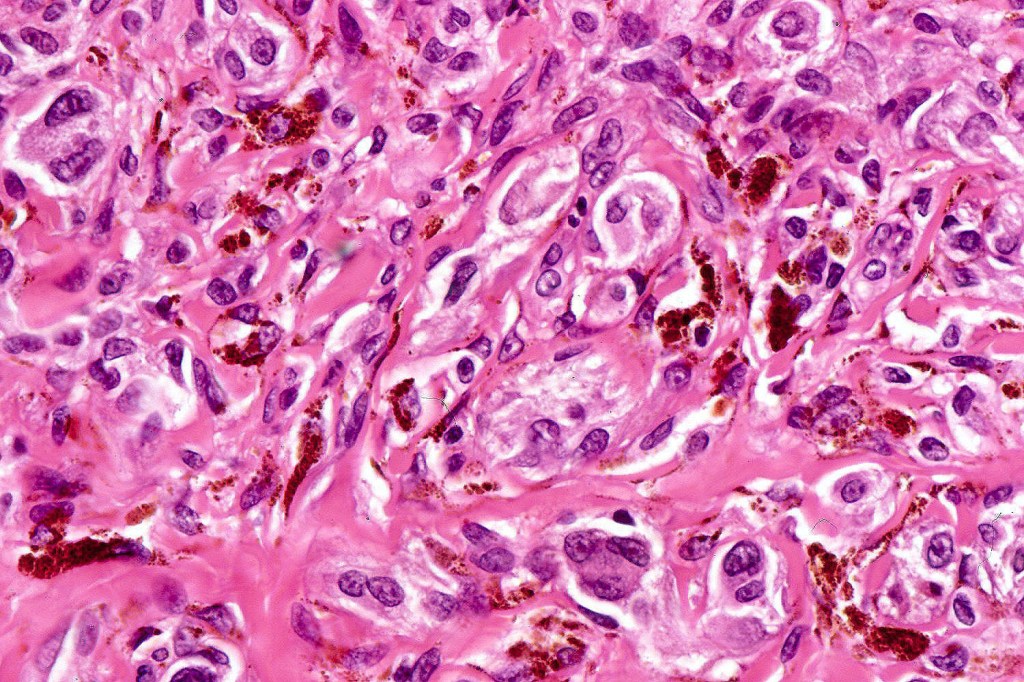

Cellular blue nevus

Histological features

•Most characteristic is the dumbbell silhouette although a plague morphology may also be encountered

•Combined nevus variant

•Admixture of spindle cells, pigmented bipolar or dendritic cells & melanophages

•Cytoplasm is pale and nuclei are small with inconspicuous nucleoli

•An alveolar pattern is characteristic particularly with clear cell nodules

•Mitoses are typically very sparse or absent

•No atypical mitoses

•No Necrosis or lymphovascular invasion

•Multinucleate giant cells sometimes present

•Stromal fibrosis, myxoid change, vascular hyalinization with cyst formation are often seen

•Some tumors are composed spindle cells in a fascicular or neuronevoid pattern

•Perineural involvement may be seen

•Balloon cell change

•Desmoplastic variant

•Hypopigmented variant